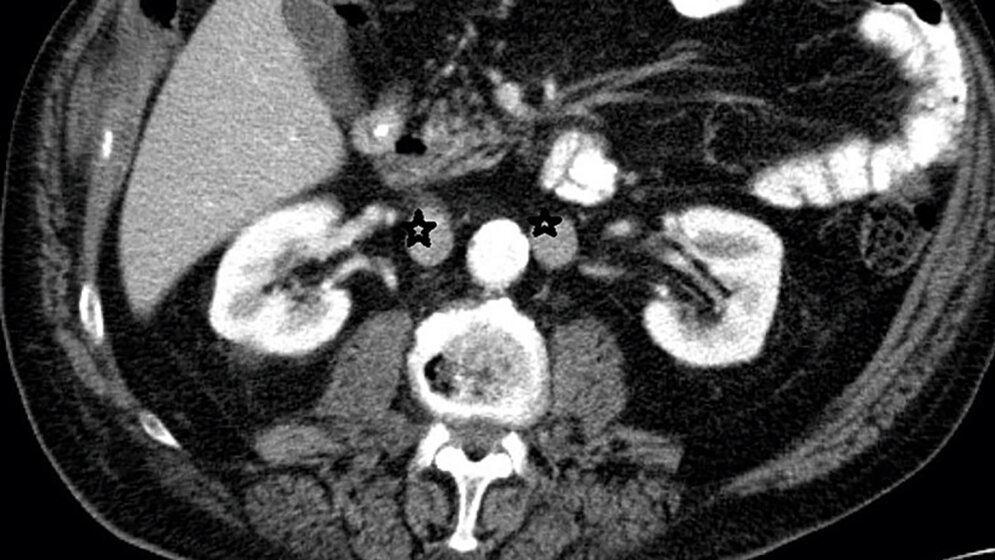

Die Doppelanlage der Vena cava inferior (VCI) ist die am häufigsten vorkommende Anomalie des venösen Gefäßes. Sie hat eine große Bedeutung bei retroperitonealen chirurgischen Eingriffen und venösen radiologischen Interventionen.

Duplication of the inferior vena cava (IVC) is the most common anomaly to affect the vena cava. Duplicated IVC has a significant relevance for retroperitoneal surgery and venous interventional radiology.